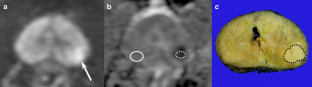

PI-RADS version 2: quantitative analysis aids reliable interpretation of diffusion-weighted imaging for prostate cancer

The rate of inter-reader disagreement for DWI score ≥4 was 11.8% (9/76). ADC ratios were higher in concordant vs. discordant DWI scores ≥4 (median, 1.7 vs. 1.1–1.2; p < 0.001). For DWI scores ≥4, the AUCs of ADC ratios were 0.970 for reader 1 and 0.959 for reader 2. In patients with an ADC ratio >1.3, the rate of inter-reader disagreement for DWI score ≥4 decreased to 5.9–6.0%. An ADC ratio >1.3 yielded 100% (reader 1, 54/54; reader 2, 51/51) positive predictive value for clinically significant cancer.